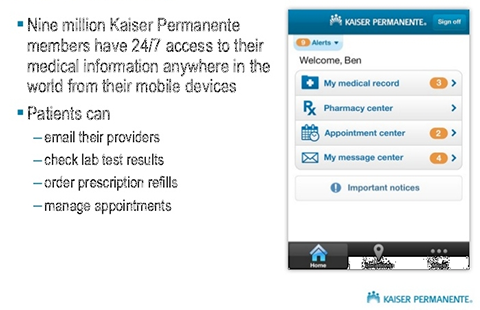

USAA ~ Safeway ~ Limited Brands ~ Macy's ~ Sears ~ Emporium ~ Nokia ~ Motorola ~ Samsung ~ LG ~ BlackBerry ~ HTC ~ Wal-Mart Stores ~ CVS ~ Best Buy ~ Rite Aid ~ Nike ~ GAP ~ J. C. Penney ~ Chevron ~ General Electric ~ AT&T ~ Hewlett-Packard ~ Bank of America Corp. ~ Citigroup ~ Berkshire Hathaway ~ International Business Machines ~ McKesson ~ Kaiser Permanente ~ Kaiser Hospitals ~ U.C.S.F ~ Stanford University School of Medicine/Medical Center ~ Sutter Healthcare ~ California Pacific Medical Center ~ San Francisco General Hospital And Medical Center ~ San Francisco VA Medical Center ~ U.S. Department of Transportation ~ U.S. Department of Homeland Security ~ Exar ~ Boeing ~ AIS ~ Siemens ~ Kaiser People Solutions ~ Cardinal Health ~ Procter & Gamble ~ UnitedHealth Group ~ Kroger ~ Marathon Oil ~ Costco Wholesale ~ Home Depot ~ Target ~ Johnson & Johnson ~ Morgan Stanley ~ State Farm Insurance ~ Dell ~ Boeing ~ Microsoft ~ Walgreen ~ United Technologies ~ Dow Chemical ~ MetLife ~ Wells Fargo ~ United Parcel Service ~ Caterpillar ~ Lowe's ~ Sears Holdings ~ Cisco Systems ~ Johnson Controls ~ FedEx ~ Intel ~ Sysco ~ Comcast ~ Coca-Cola ~ American Express ~ Aetna ~ Motorola ~ Allstate ~ Prudential Financial ~ Tyson Foods ~ Staples ~ Delta Air Lines ~ City and County of Sacramento ~ City and County of San Francisco ~ City and County Oakland ~ San Jose International Airport ~ JFK International Airport